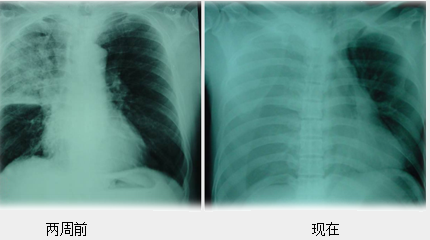

③2周前胸片右肺上叶大片状阴影。(1分)

③影像学:1周前胸片右侧胸腔均匀密度增高影,肋膈角消失,超声检查:右侧胸腔大量积液,部分回声不均,有絮状物沉积。(0.5分)